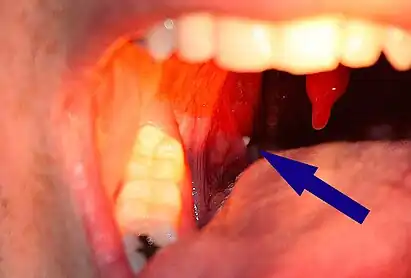

A tonsillolith lodged in the tonsillar crypt

Tonsil stones, also known as tonsilloliths, are mineralizations of debris within the crevices of the tonsils.[1][3] When not mineralized, the presence of debris is known as chronic caseous tonsillitis (CCT).[1] Symptoms may include bad breath,[1] foreign body sensation, sore throat, pain or discomfort with swallowing, and cough.[4] Generally there is no pain, though there may be the feeling of something present.[1] The presence of tonsil stones may be otherwise undetectable, however some people have reported seeing white material in the rear of their throat.

Larger tonsil stones may cause recurrent bad breath, which frequently accompanies a tonsil infection, sore throat, white debris, a bad taste in the back of the throat, difficulty swallowing, ear ache, and tonsil swelling.[12] A medical study conducted in 2007 found an association between tonsilloliths and bad breath in patients with a certain type of recurrent tonsillitis. Among those with bad breath, 75% of the subjects had tonsilloliths, while only 6% of subjects with normal halitometry values (normal breath) had tonsilloliths. A foreign body sensation may also exist in the back of the throat. The condition may also be an asymptomatic condition, with detection upon palpating a hard intratonsillar or submucosal mass.